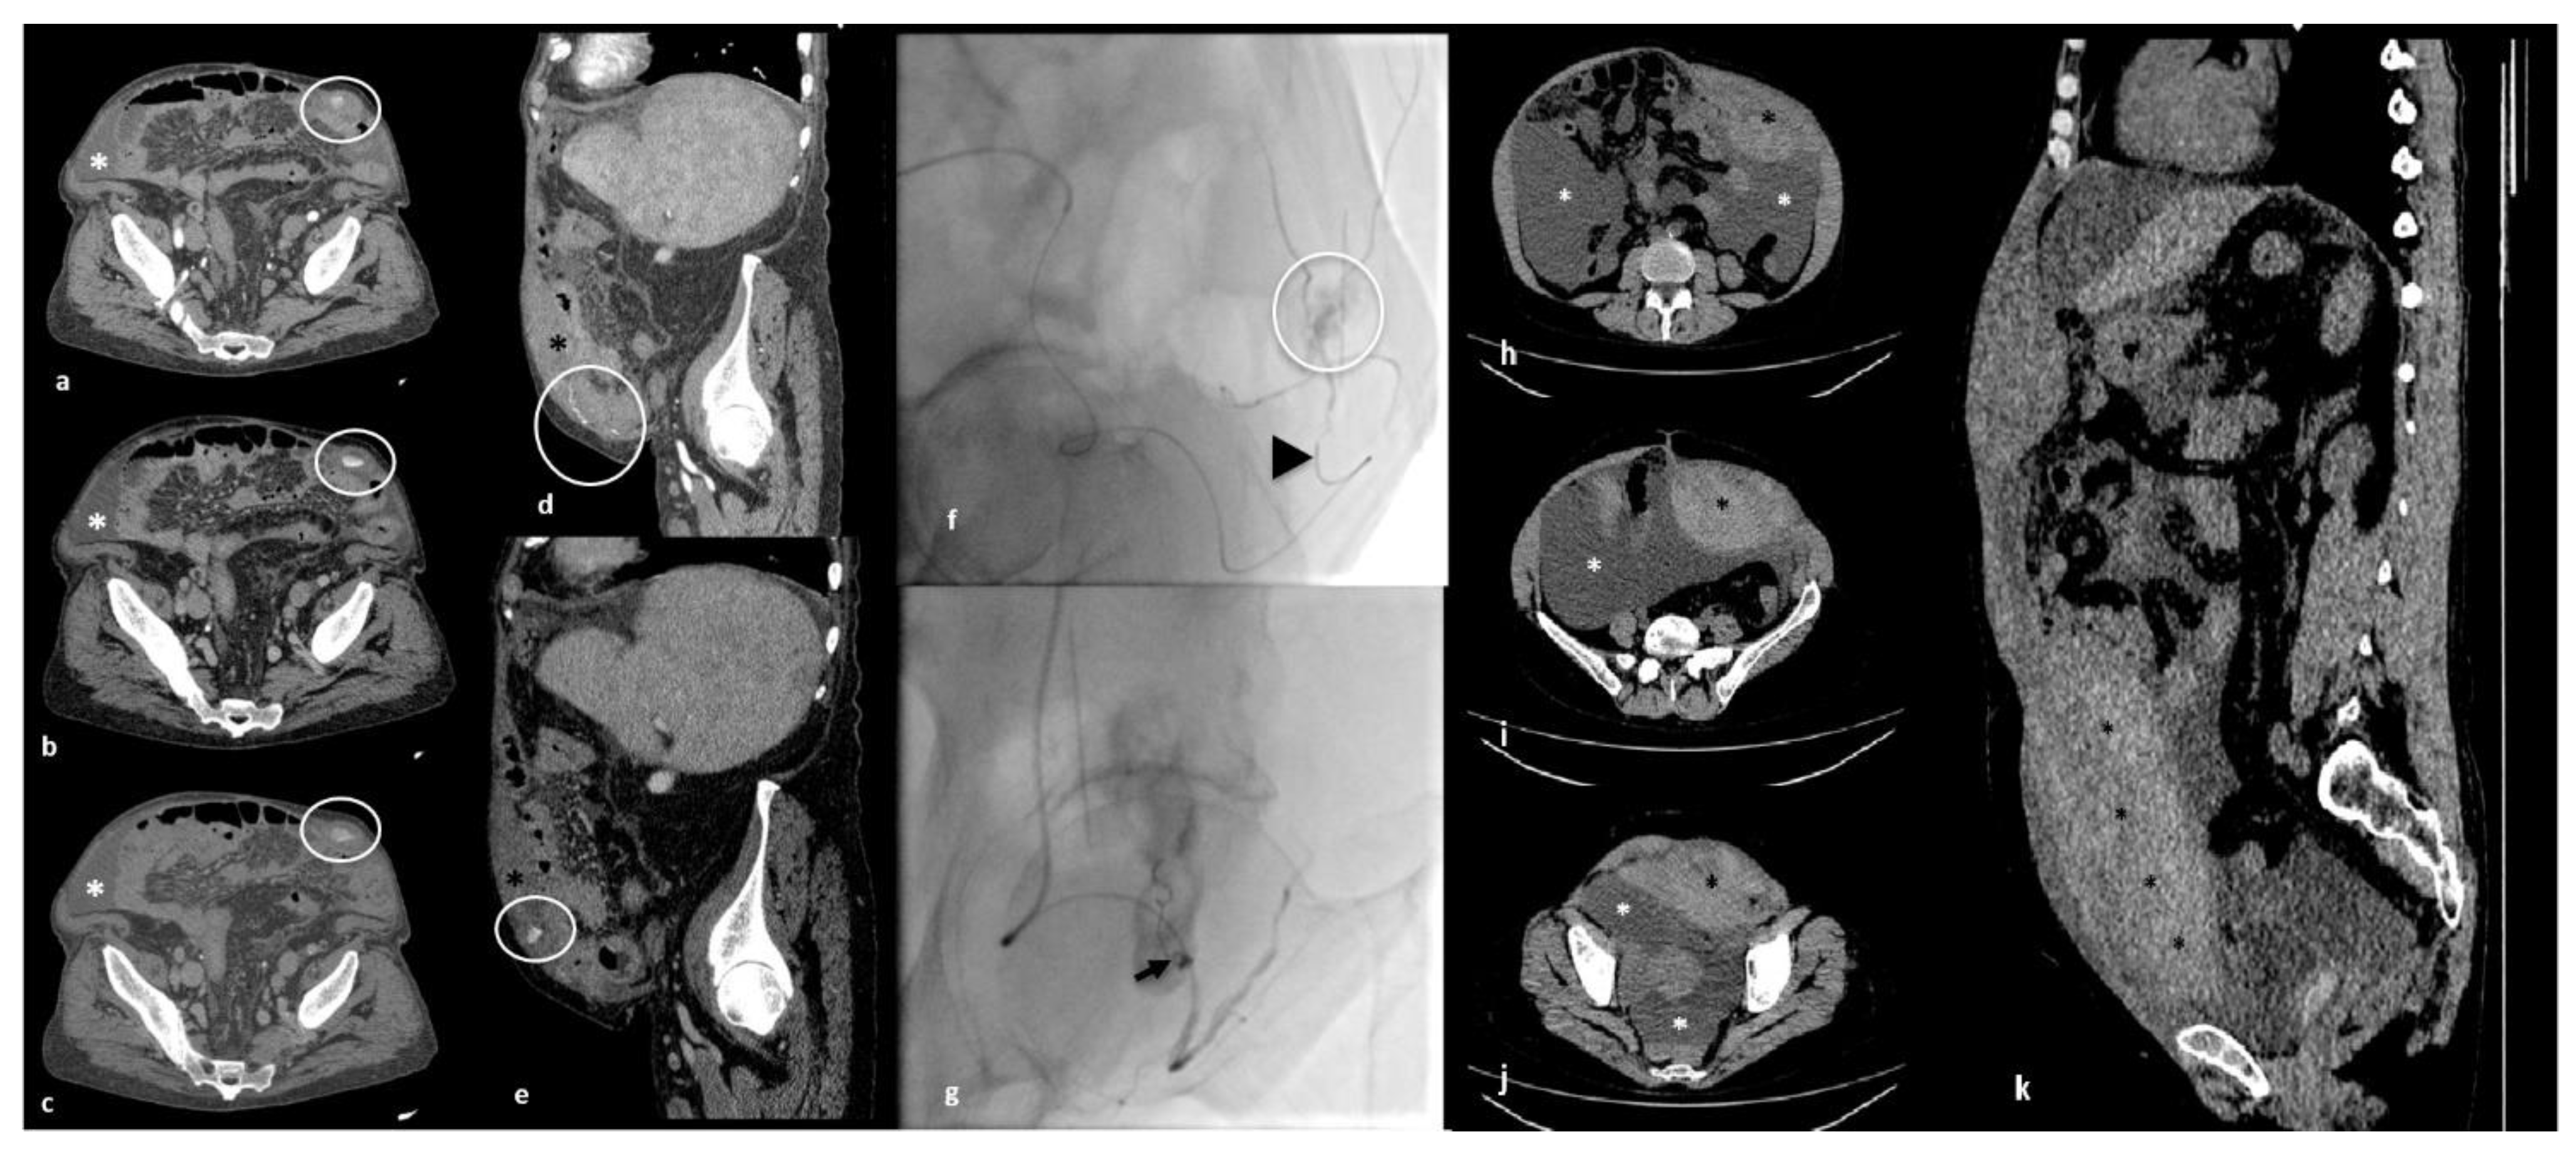

| Abdomen and pelvis CT scan angiography findings | A coarse collection of blood density in the context of the muscular planes of the left iliac fossa, showing contextual active bleeding strictly contiguous to the distal third of the inferior epigastric artery | A large blood collection in the context of the anterolateral wall of the abdomen in the subfascial area measuring about 14 × 7.5 cm in the axial section |

| Therapeutic approach | Percutaneous transcatheter arterial embolization | Conservative approach |